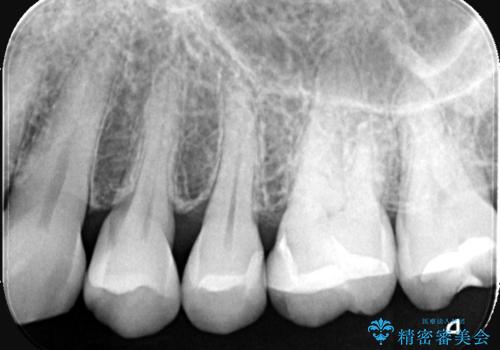

- 左上5番と6番の奥歯に入っている金属の詰め物(メタルインレー)の見た目を改善したいという主訴でご来院されました。お口の中の金属をなくしたいという患者様のご希望を踏まえ、天然歯に近い色と質感を持つセラミックインレーに交換する治療計画を立案。これにより、見た目の改善だけでなく、金属アレルギーのリスクを排除したメタルフリーの環境を実現することを目指しました。

治療では、まず古い金属のインレーを慎重に取り外しました。金属の下に隠れていた虫歯の再発がないかを確認し、歯を丁寧に形成。その後、精密な型取りから患者様の歯の色に合わせたオーダーメイドのセラミックインレーを作製しました。セラミックは、自然な光の透過性を持つため、周囲の歯と区別がつかないほどの美しい仕上がりとなります。適合性の高いセラミックインレーを装着することで、再発のリスクを抑えつつ、長年のコンプレックスだった銀歯がなくなり、笑顔でも気にならない自然な奥歯を取り戻していただけました。